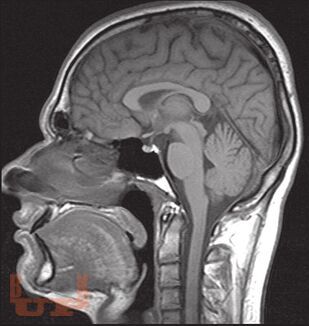

«Атлас нормальной анатомии магнитно-резонансной и компьютерной томографии головного мозга» посвящен актуальной проблеме нейроморфологии и краниологии — прижизненной макроскопической характеристике головного мозга и черепа с применением современных методов визуализации — магнитно-резонансной томографии и компьютерной томографии.

В Атласе представлены более 500 томограмм: магнитно-резонансные томограммы головного мозга, магнитно-резонансные ангиограммы головного мозга, магнитно-резонансные томограммы черепных нервов, компьютерные томограммы головного мозга, компьютерные ангиограммы сосудов головного мозга. Выполнена компьютерная реконструкция костей черепа, дана подробная информация об одном из сложнейших объектов черепа человека — височной кости.

Представленные томограммы могут заинтересовать специалистов в области магнитно-резонансной и компьютерной диагностики не только в качестве эквивалента нормы головного мозга, но и в пределах достаточно широкого диапазона индивидуальной анатомической нормы.